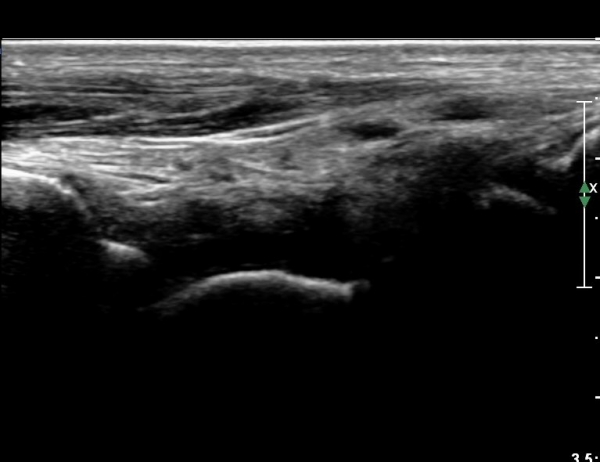

¹ß¸ñ ¾ÕÂÊ Á¾´Ü¸é°Ë»ç¿¡¼­ °üÀý³» ºÎÁ¾À» º¸ÀδÙ(»çÁø 1).

°üÀý³» ºÎÁ¾Àº ½É°¢ÇÑ ¼Õ»óÀ» ¾Ï½ÃÇÏ´Â ¼Ò°ßÀÌ´Ù.